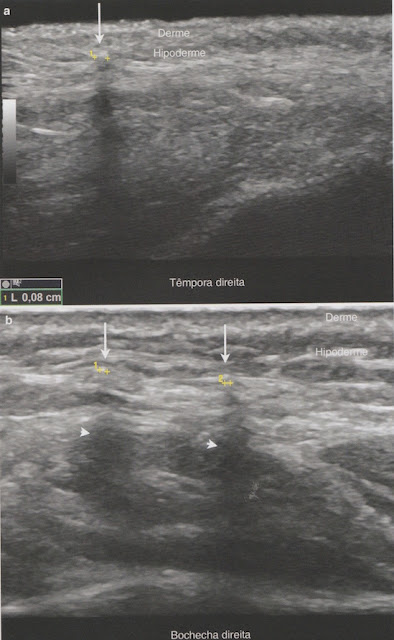

- Áreas com ausência ou diminuição de tecido adiposo hipoecogênico.

- Aumento da ecogenicidade da hipoderme.

- Áreas com diminuição de tecido adiposo e hiperecogenicidade da hipoderme.

- Septos hipodérmicos fibrosos hiperecogênicos brilhantes e às vezes espessos.

- Sombra posterior devido fibrose proeminente.